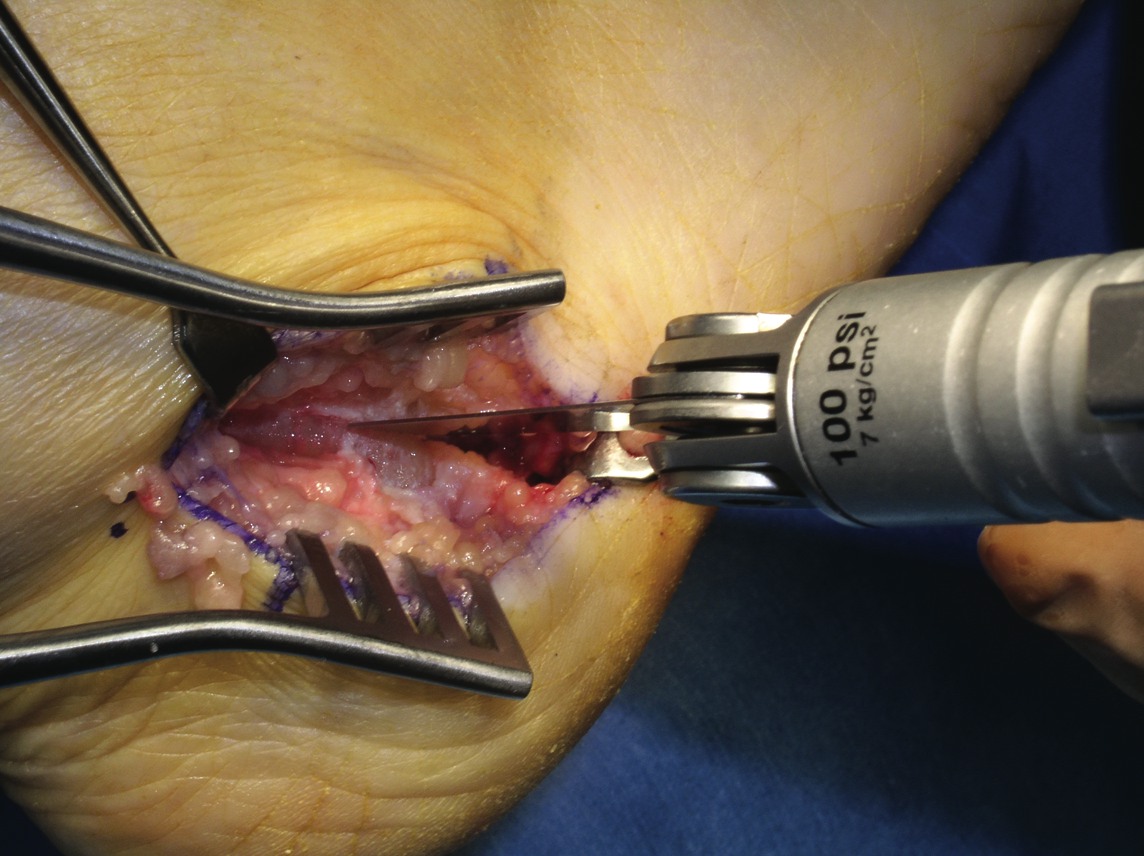

Adult-acquired flatfoot (AAF) is one of the more common conditions that podiatrists see in practice. With this in mind, some of the leading experts on this subject shared their views and experience on this subject. They discuss the role of diagnostic imaging, their use of conservative treatments and their perspectives on appropriate surgical procedures. Without further delay, here is what they had to say. Q: What ancillary studies are required for proper diagnosis and treatment selection for the adult-acquired flatfoot? A: Michael S. Lee, DPM, says AAF is generally a clinical diagnosis. Other than the physical exam, Shannon Rush, DPM, says a proper radiographic evaluation is the most important aspect of diagnosing AAF and arriving at an appropriate course of treatment. Dr. Rush emphasizes the inclusion of foot and ankle views as well as hindfoot alignment and long leg calcaneal views. All the panelists agree that neutral position X-rays are helpful in determining the degree of the deformity and what procedure one should perform. Alan Catanzariti, DPM, says it is important to evaluate the talus-first metatarsal angle on both AP and lateral radiographs. He adds that the AP views also enable one to see the amount of talar head that is covered by the navicular. Standard radiographs also allow clinicians to assess the tritarsal complex for degenerative changes, according to Dr. Catanzariti. He says these degenerative changes may indicate an arthrodesis procedure as opposed to performing reconstructive osteotomies or soft tissue procedures. The majority of the panelists recommend obtaining ankle X-rays in order to detect valgus deformity within the ankle. When there is valgus deformity within the ankle joint, Dr. Catanzariti will typically consider performing a medial displacement osteotomy of the calcaneus. “This helps decrease the tension within the deltoid ligament and prevent further attenuation of medial soft tissue structures,” explains Dr. Catanzariti. In cases of end-stage flatfoot deformity, Jordan Grossman, DPM, says AP ankle views are useful in evaluating for deltoid ligament insufficiency and valgus deformity of the talus within the ankle mortise. Gerard V. Yu, DPM, and Dr. Catanzariti agree with Dr. Rush about the value of obtaining long leg axial films. Dr. Catanzariti says long leg axial views and Saltzman views allow one to evaluate the calcaneus, subtalar joint, ankle joint and tibia relative to one another. He adds that these views often facilitate appropriate procedure selection. Lower-extremity alignment views may also be indicated in certain instances, according to Dr. Rush. Dr. Grossman concurs, noting that obtaining Cobey and hindfoot alignment views are useful in severe cases and with lower-extremity deformity. When it comes to magnetic resonance imaging (MRI), Dr. Rush says he “rarely, if ever” uses it in his workup for AAF. Dr. Catanzariti agrees. However, if he is contemplating arthrodesis versus reconstruction, Dr. Catanzariti will sometimes obtain a MRI in order to detect early degenerative changes within the subtalar joint that are subtle on standard X-rays. Dr. Grossman concurs, noting that MRI is indicated in “select circumstances” in which the diagnosis is unclear. Dr. Lee says one may employ MRI or ultrasound imaging to evaluate the posterior tibial tendon for attenuation or complete rupture. Dr. Yu emphasizes that MRI is most helpful when clinicians use a facility that has an experienced musculoskeletal radiologist, who is knowledgeable about the clinical entity and its primary and secondary manifestations. “I believe the MRI should be part of the standard workup for AAF if you plan to do direct surgical repair alone or as part of the correction of the deformity,” maintains Dr. Yu. Dr. Lee adds that a CT scan may have limited use in determining the degree of arthrosis in stage 3 or stage 4 deformities. Gait analysis may also be helpful in procedure selection, according to Dr. Catanzariti. Q: What is the significance of the posterior tibial tendon in the adult-acquired flatfoot? A: Dr. Yu says the primary purpose of the posterior tibial tendon is decelerating internal rotation of the tibia and accordingly limiting pronation of the foot following heel strike in gait. The intrinsic pathology specific to the posterior tibial tendon is “insignificant once the deformity has occurred,” notes Dr. Rush. He says the most important overriding factor is that the tendon has functionally weakened and is unable to stabilize the midtarsal joint. Dr. Rush says this functional weakness may be due to posterior tibial tendon dysfunction (PTTD) or subluxation in the rearfoot. The posterior tibial tendon plays “a primary role in the development of AAF,” according to Dr. Grossman. Dr. Lee says the posterior tibial tendon plays an important role early in the process but its importance diminishes as the deformity progresses. He notes the spring ligament may become attenuated in some situations. While there are several possible causes of AAF, Dr. Grossman says insufficiency or rupture of the posterior tibial tendon is the most common cause. The posterior tibial tendon often may be attenuated or diseased in AAF, according to Dr. Catanzariti, but he says this can vary from patient to patient. If patients have significant symptoms as a direct result of disease within the posterior tibial tendon, Dr. Catanzariti says they may require surgical intervention, which could include a tenosynovectomy, a partial tendon debridement or actual resection of an attenuated tendon. He notes these interventions may be supported by tendon transfers. In these cases, Dr. Catanzariti prefers a flexor digitorum longus tendon transfer. Dr. Rush says the clinical view of the posterior tibial tendon or its appearance on MRI does not influence one particular reconstruction over another. When it comes to stage 3 and stage 4 AAF, Dr. Lee says the posterior tibial tendon plays little importance in function, diagnosis or surgical treatment selection. If a patient has a predisposition to excessive pronation due to a specific foot structure, Dr. Yu says the posterior tibial tendon is “very significant.” When patients have a cavus foot, he notes the inherent stability of the foot will limit pronation. However, if a patient has hypermobile joint laxity syndrome, Dr. Yu says the posterior tibial tendon will be more important as it will “work harder to prevent excessive pronation.” If one stabilizes the foot well with osseous procedures, especially fusions, the importance of the posterior tibial tendon for function decreases, according to Dr. Yu. When one performs a posterior tibial tendon transfer for other conditions (i.e., dropfoot deformity), Dr. Yu says the foot structure remains the same due to the inherent interlocking of osseous units. When performing a triple arthrodesis, Dr. Yu notes the surgeon can leave the PT tendon alone altogether unless the pain there is due to active inflammation around the tendon itself. In essence, the more inherently stable the foot is, whether by surgical fusion or anatomical stability, the less important the PT tendon is to overall foot function. Q: What conservative measures have been successful in your hands in the treatment of AAF? A: Employing orthotics in combination with antiinflammatory medications and posterior muscle group stretching provides relief in milder cases of AAF, according to Dr. Catanzariti. When it comes to stage 1 conditions, Dr. Lee notes he has had a fair amount of success utilizing figure-of-eight ankle braces along with rest, ice, NSAIDs and shoe gear modifications. He notes that stage 2 deformities have responded well to prefabricated and custom orthotics, rest, activity modification and NSAIDs. Dr. Lee has also utilized ankle foot orthoses (AFOs). Depending on the presentation and degree of the deformity, Dr. Grossman says he has had success with the aforementioned modalities as well as physical therapy, cast immobilization and a removable walking boot. Functional orthotics may be helpful in the early stage of AAF but Dr. Yu says he generally does not use them. Dr. Yu notes that some companies make a variety of orthotic devices that “are too flimsy and do not have enough substance to do the job.” Essentially, one needs to ensure bracing of the foot to the leg, according to Dr. Yu, especially in the presence of other factors like obesity, genu valgum, etc. Dr. Yu says Aircast ankle braces and similar devices may provide good relief prior to using the more sophisticated and expensive devices like the Richie Brace and AFOs. With chronic conditions, Dr. Rush will use aggressive custom orthoses, Richie Braces and the Arizona AFO prior to surgical intervention. With stage 3 and stage 4 deformities, Dr. Lee will brace them with either UCBL orthotics or AFOs. If these fail, he proceeds to surgical intervention. The other panelists concur that one can use conservative bracing for stage 3 and stage 4 deformities in patients who are not surgical candidates. In these patients, Dr. Rush has had success with the Arizona AFO while Dr. Catanzariti has utilized supramalleolar AFOs with good results. In regard to conservative therapy, Drs. Rush and Yu say there are many factors to consider including the patient’s level of activity, weight loss, patient education, proper shoe gear and rehabilitation. Realistic expectations are essential and become more important as patients progress from stages 1 to 4, according to Dr. Yu. He says a patient with stage 3 or 4 deformity and low activity may respond surprisingly well to bracing but bracing is unlikely to be successful in a highly active patient with stage 2 AAF. Q: At what point does AAF become a surgical foot? A: The majority of the panelists consider surgical treatment when the deformity is progressive, grossly unstable and doesn’t respond to functional bracing. Dr. Rush says the potential progression of the deformity is a significant concern. “Severe talonavicular and subtalar subluxation can have a devastating influence on the ankle joint,” emphasizes Dr. Rush. “If the lateral peritalar drift is left unabated, the ankle can also fall into valgus.” Dr. Lee says he performs surgery for end-stage deformities such as stage 3 and stage 4 conditions. However, Dr. Yu notes that even severe deformities do not justify surgery alone. “If the other foot is flat and asyptomatic, you may be able to manage the pathologic foot without surgery,” points out Dr. Yu. If bracing fails, one needs to turn to surgical options, according to Dr. Yu. He emphasizes that physicians should always remember to treat patients in conjunction with their disease or deformity and not the X-rays. He notes that clinical correlation is essential to effective treatment. Q: When are calcaneal osteotomies indicated in the treatment of AAF? A: Dr. Yu says these procedures are “rarely” indicated for treating AAF. He believes this approach has been abused in an attempt to avoid more time-tested techniques, such as the gold standard triple arthrodesis, especially in the later stages of AAF when the deformity can be quite severe. In his experience, Dr. Yu says the calcaneal osteotomy has little impact in resolving severe AAF “when a fusion in conjunction with tibialis posterior repair and posterior lengthening would have worked out better.” While he notes that calcaneal osteotomies are very helpful in the earlier stages of the disease, Dr. Yu emphasizes that many of these patients will do well without surgery. Drs. Grossman, Catanzariti and Lee believe calcaneal osteotomies are primarily indicated for flexible or reducible deformities. These procedures allow surgeons to correct various deformities while maintaining midtarsal and subtalar joint motion, according to Dr. Grossman. He says this will “most likely decrease the likelihood of adjacent joint demand and arthrosis that one commonly sees with an isolated or triple arthrodesis.” Citing the versatility of calcaneal osteotomies, Dr. Catanzariti calls them an excellent alternative to arthrodesis procedures. “These osteotomies spare the tritarsal complex and allow the hindfoot to function in a relatively normal fashion,” explains Dr. Catanzariti. Dr. Lee concurs. If the flatfoot is supple, he says one can achieve correction with calcaneal osteotomies while preserving most of the hindfoot motion. When it comes to late stage 1 AAF, Dr. Catanzariti will consider posterior calcaneal displacement osteotomies and sometimes uses this approach to treat early stage 2 conditions. Dr. Lee utilizes posterior calcaneal displacement osteotomies for early stage 2 AAF and employs the Evans calcaneal osteotomy and double osteotomies for late stage 2 conditions. For mid- to late stage 2 AAF, Dr. Catanzariti considers performing an anterior open wedge osteotomy in combination with a posterior displacement osteotomy. Dr. Rush says calcaneal osteotomies are a “wonderful surgical tool” for treating AAF. He performs a posterior osteotomy with any valgus malalignment of the subtalar joint when a subtalar arthrodesis is not indicated. Obtaining hindfoot alignment and long leg calcaneal axial views help in planning with this procedure, according to Dr. Rush. He maintains that clinicians must be careful to evaluate the midtarsal joint and medial column for instability and supinatus. In the presence of instability or deformity, Dr. Rush notes one must add ancillary procedures in order to stabilize the medial column. Dr. Rush adds that naviculocuneiform arthrodeses serve to stabilize the medial column and address the naviculocuneiform fault if one exists. Dr. Grossman says he typically performs calcaneal osteotomies in combination with other bony and/or soft tissue procedures. Dr. Rush does not utilize an isolated anterior calcaneal osteotomy for AAF. He says one must combine this procedure with the posterior osteotomy to correct the valgus and lateral translation in the subtalar joint. Dr. Rush strongly emphasizes paying close attention to the subtalar alignment when selecting these procedures. Dr. Lee also notes that he prefers calcaneal osteotomies over isolated hindfoot fusions when treating AAF in smokers, more active patients and those with a normal or slightly elevated body mass index (BMI). Q: When is an isolated or combined joint arthrodesis indicated in treating AAF? A: According to Dr. Yu, these procedures are indicated when there is significant deformity with significant disability and symptoms, especially in cases that involve degenerative arthritis or excessive mobility that cannot be predictably controlled by other means. When one considers performing three joint preservation procedures, Dr. Yu believes one joint fusion can achieve the same outcome. He says performing an isolated joint fusion is especially beneficial for patients who have a low level of activity and want relief of their pain and a stable foot. If one achieves the fusion in a neutral position without varus or valgus, Dr. Yu says the fusion provides “exceptional functional outcomes” with minimal stress on adjacent joints, which minimizes the risk of subsequent degenerative joint disease. “It’s all about the alignment and position of fusion,” emphasizes Dr. Yu. Over the years, Dr. Yu notes anecdotally that he has observed, examined and analyzed a large number of adult patients who had congenital coalitions, realizing they had minimal to no symptoms until their late 40s and 50s or even later. Dr. Yu says the position of the fusion is key to minimizing stress on adjacent joints and structures. Tarsal coalition patients who present early in life invariably have peroneal spastic flatfoot deformities, creating a completely different clinical problem, according to Dr. Yu. However, he emphasizes that the technique one uses to perform these fusions is important. Rigid deformities, a degenerative midtarsal or subtalar arthritis are the primary indications for using isolated or combined arthrodesis procedures, according to Dr. Grossman. He says one may also consider these procedures for obese patients with AAF or in cases of underlying inflammatory arthritis. Dr. Grossman says he typically combines an isolated arthrodesis procedure with soft tissue reconstruction and posterior muscle group lengthening. As with all arthrodesis procedures, Dr. Grossman says the position primarily predicates outcomes and patient satisfaction. Dr. Lee utilizes isolated hindfoot fusions in late stage 2 deformities when there may be mild arthrosis in one or more of the hindfoot joints, when the deformity is severe on plain radiographs or in patients with a higher BMI. A subtalar joint arthrodesis may be effective in the presence of isolated subtalar joint disease or arthritis, according to Dr. Catanzariti, but he rarely uses this procedure to treat AAF. In these cases, Dr. Catanzariti prefers a double calcaneal osteotomy for stage 2 AAF, a triple arthrodesis for stage 3 AAF and a combination of triple arthrodesis and posterior calcaneal displacement osteotomy for stage 4 AAF. On the other hand, Dr. Lee says he tends to perform an isolated subtalar joint arthrodesis in many cases of AAF but will occasionally opt for talonavicular arthrodesis in more severe cases of AAF with significant talar declination. Dr. Rush notes that painful degenerative joints and significant subluxation in the subtalar or talonavicular joints are general indications for arthrodesis. Arthrodesis of the non-essential medial column joints, such as the naviculocuneiform or metatarsocuneiform joints, can easily and effectively stabilize the medial arch, according to Dr. Rush. He adds that combining this procedure with calcaneal osteotomies can “correct most degrees of instability.” While distraction fusions are effective for lateral peritalar subluxation, Dr. Rush cautions that they often do not address the valgus or translation in the subtalar joint. According to Dr. Lee, distraction arthrodesis of the calcaneocuboid joint is a powerful procedure but does have “some elevated risk of non-union.” In the presence of supinatus or varus deformities, all the panelists agree that one must perform some type of ancillary medial column procedure, whether it is a medial column fusion or an osteotomy. Dr. Mendicino is Chief of the Division of Foot and Ankle Surgery at the Western Pennsylvania Hospital in Pittsburgh. He is a Fellow and Past President of the American College of Foot and Ankle Surgeons, and is a Clinical Professor of Surgery at the Western Campus of the Temple University School of Medicine. Dr. Catanzariti is the Director of the Residency Training Program within the Division of Foot and Ankle Surgery at the Western Pennsylvania Hospital in Pittsburgh. He is a Fellow of the American College of Foot and Ankle Surgeons. Dr. Grossman is Chief of the Section of Podiatry at Akron General Medical Center in Ohio. He is a Fellow of the American College of Foot and Ankle Surgeons, and a Diplomate of the American Board of Podiatric Surgery. Dr. Lee is a Fellow and serves on the Board of Directors of the American College of Foot and Ankle Surgeons. He is a Diplomate of the American Board of Podiatric Surgeons. He recently chaired the adult flatfoot panel and co-authored the ACFAS Clinical Practice Guidelines for Adult Flatfoot. He is in private practice at Central Iowa Orthopedics in Des Moines, Iowa. Dr. Rush is a Fellow of the American College of Foot and Ankle Surgeons. He is a Staff Surgeon within the Department of Orthopedics at Kaiser Permanente in Walnut Creek, Ca. Dr. Rush is also a Staff Surgeon with the San Francisco Bay Area Foot and Ankle Residency Program. Dr. Yu is the Director of the Podiatric Surgical Residency Program (PSR-36) and is the Chief of the Section of Podiatry of the Division of Orthopedic Surgery at the St. Vincent Charity Hospital, and at the Huron Hospital in Cleveland. He is a Fellow of the American College of Foot and Ankle Surgeons, and is a Diplomate of the American Board of Podiatric Surgery. Dr. Yu is also the Director of Program Development and a faculty member of the Podiatry Institute.